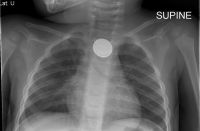

The key to differentiating a button battery from a coin is to magnify or zoom into the image looking for a double ring or halo. This x-ray shows a small ridge on the object that this toddler has swallowed – a button battery.

Researchers also recommend that manufacturers ensure that packaging for batteries and products containing button batteries is child resistant and that they design all battery compartments to either require a screwdriver to be opened or that they be secured with a child-resistant locking mechanism, regardless of whether the product is intended for use by children or adults. Parents who think that their child may have swallowed a button battery should seek medical attention immediately so that an x-ray can be taken to be sure that the battery is not stuck in the esophagus.